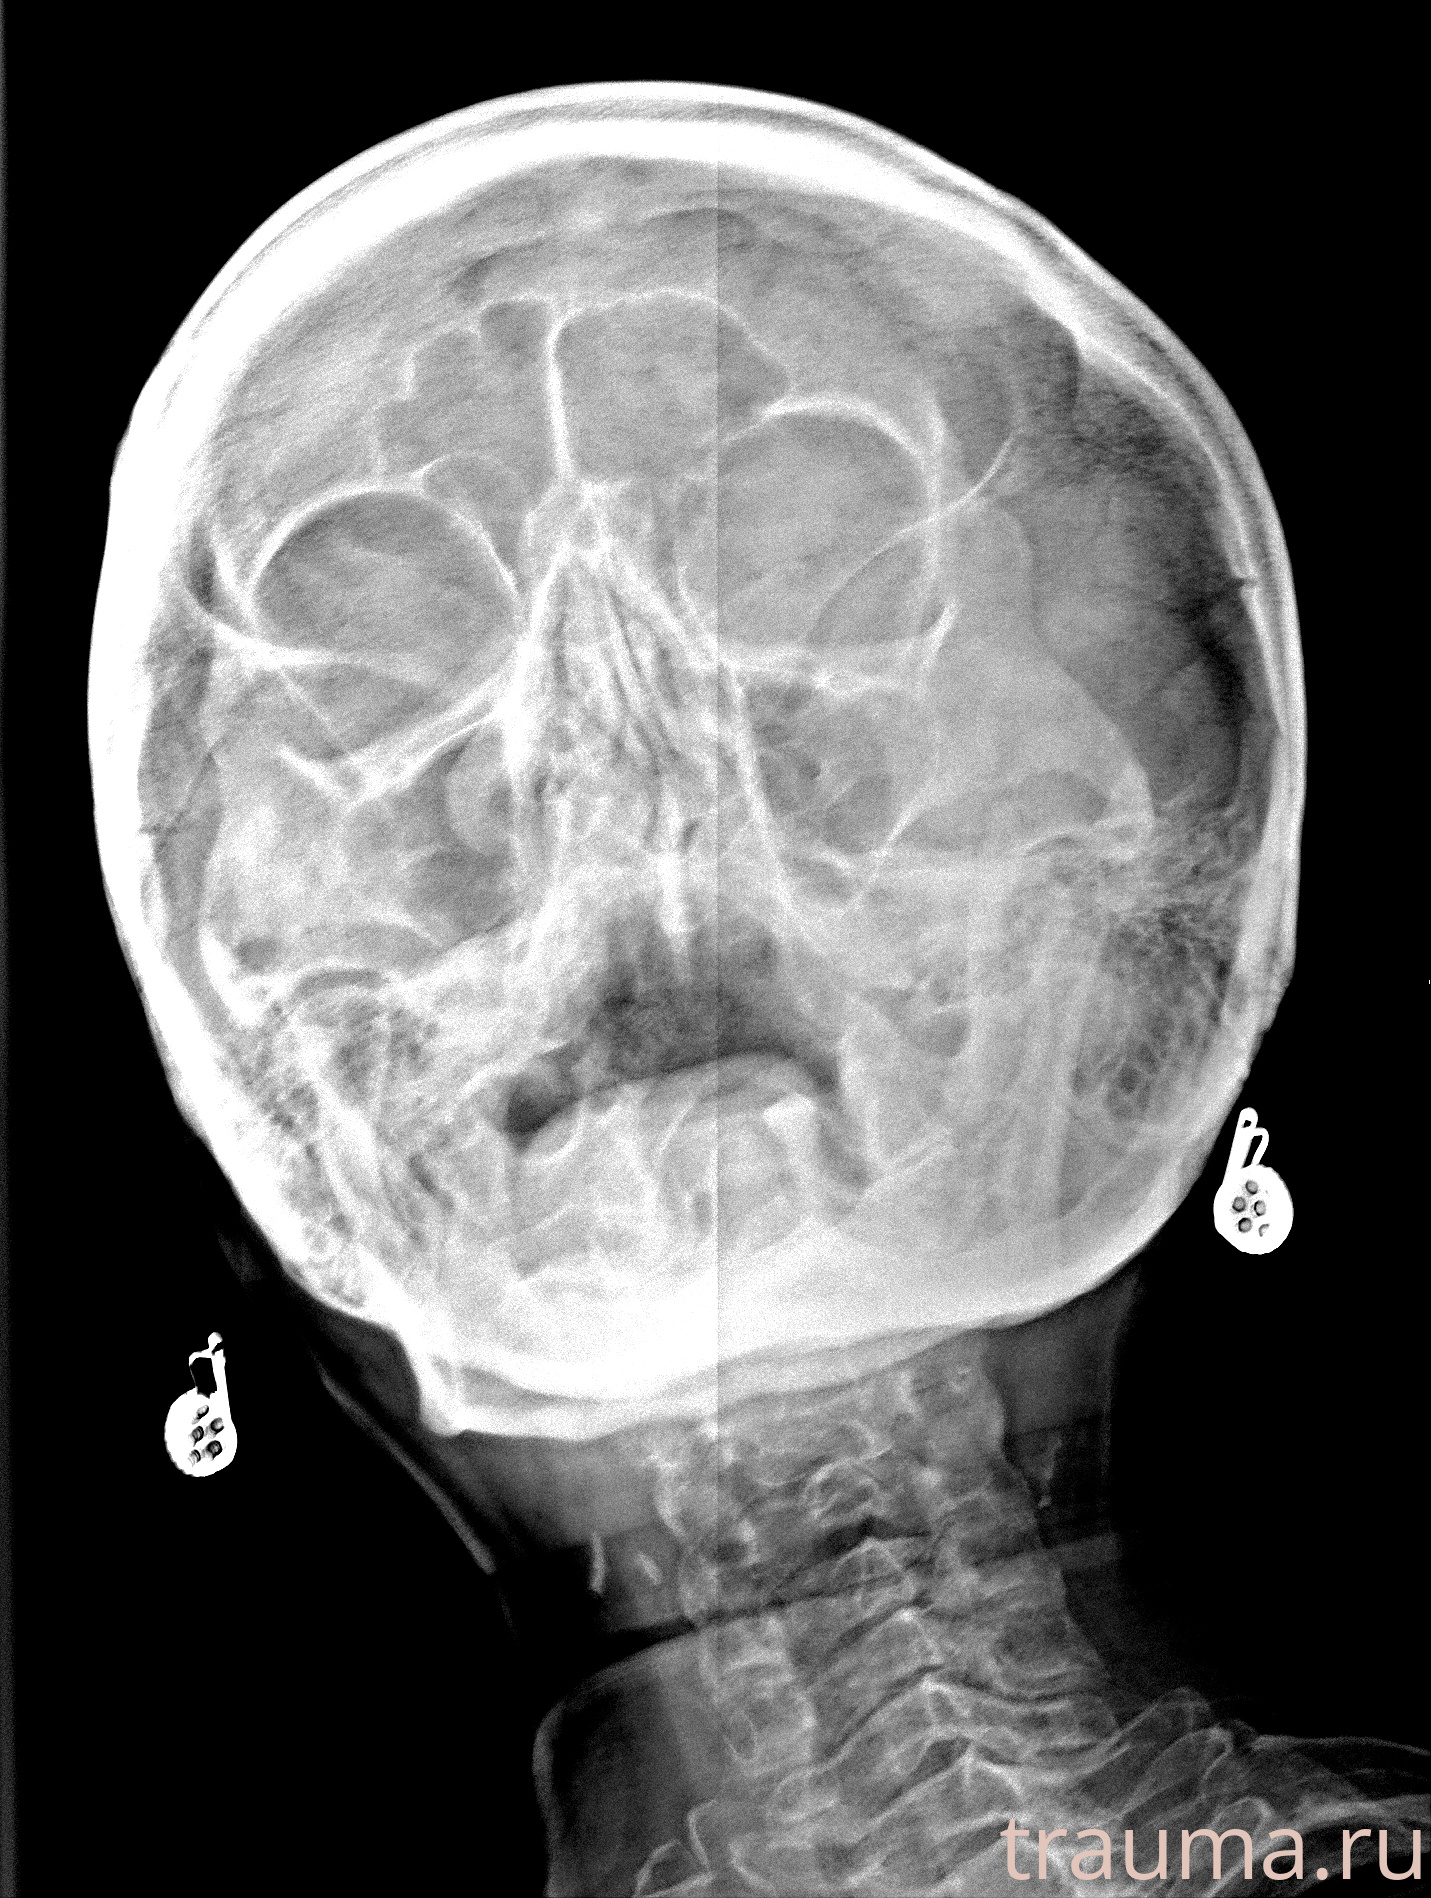

Рентгенограммы

Рентген на дому: по вашему адресу приезжает врач-рентгенолог, травматолог-ортопед с мобильным рентгеновским аппаратом, проводит диагностику травмы или заболевания, делает необходимые рентгенограммы, дает рекомендации по дальнейшему лечению. Получить качественные снимки в домашних условиях возможно благодаря уникальной методике, разработанной МосРентген Центром для института  Склифосовского

при переломе шейки бедра и пневмонии от компании МосРентген Центр - партнера Института имени Склифосовского